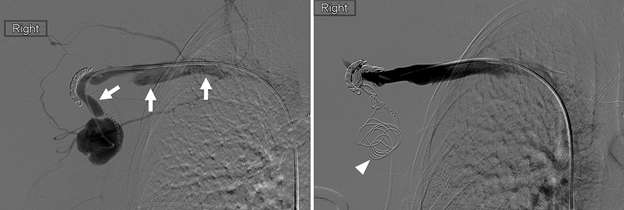

False aneurysm, or pseudoaneurysm, of the breast may be post-traumatic (blunt or penetrating), iatrogenic (e.g., post-biopsy, post-surgery), spontaneous (secondary to hemorrhage in the setting of coagulopathies or uncontrolled hypertension), or from vascular invasion by breast malignancy. The diagnosis of a breast pseudoaneurysm, if superficial, can often be made clinically by the presence of an expanding palpable, pulsatile mass on physcial exam. However, Doppler ultrasonography is the gold standard for confirming the diagnosis and characterizing the lesion for subsequent treatment planning (Figure 5). In the setting of acute trauma, breast and axillary pseudoaneurysms are usually identified radiographically during a trauma CT scan. Prompt treatment of pseudoaneurysms, especially if enlarging, is recommended in order to prevent clinically significant hemorrhage and rupture. The choice of therapy is guided by both clinical factors and imaging features, but generally involves an initial trial of manual external compression. This can be performed using an ultrasound probe, which allows the clinician to monitor treatment progress under real time visualization. More invasive intervention is warranted if there is persistent filling of the pseudoaneurysm sac, usually done in a step-wise fashion of increasing invasiveness. The first-line therapy is ultrasound-guided direct thrombin injection, which is only performed for pseudoaneurysms with features of a narrow (and preferably long) communication to the native artery origin (i.e., narrow "neck"). Thrombin injection is performed by slowly injecting a small volume of concentrated thrombin solution via direct needle puncture under constant ultrasound visualization. The procedure is well tolerated, however, there is a risk of distal embolization/migration which can lead to arterial thrombosis and ischemia; thus, thrombin injection should only be performed for pseudoaneurysms with a confidently seen narrow neck. Second-line therapies include endovascular treatment and surgical repair. Endovascular treatment is accomplished either via transarterial embolization of the sac using vascular coils and/or liquid embolic material, or by deploying a covered arterial stent across the pseudoaneurysm, thereby excluding the sac from arterial inflow. The latter is less preferable, as it requires post-treatment anticoagulation to mitigate the risk of in-stent thrombosis and stenosis. Surgical repair is generally reserved for refractory pseudoaneurysms or those with unfavorable anatomy. The operation is performed by surgically ligating across the pseudoaneurysm supply and resecting or evacuating the sac hematoma.